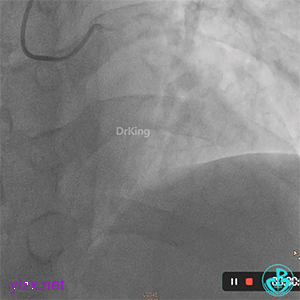

03 急诊冠脉造影

右冠脉粗大,近中段瘤样扩张明显,中段闭塞,局部可见大块血栓影。

前降支开口至近段明显瘤样扩张,中段闭塞,第一对角支粗大,无明显狭窄。

LCX发育小,内膜不光滑,血流3级。